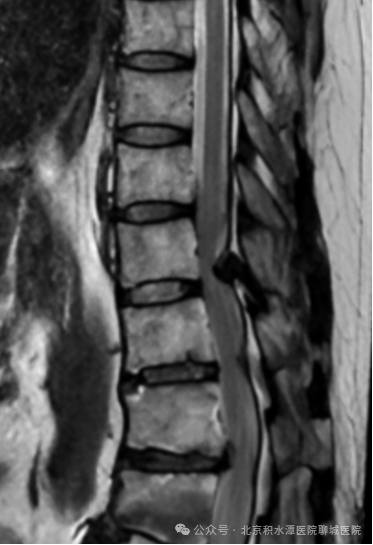

术前影像:T11/12胸椎黄韧带骨化,胸椎椎管狭窄

术后影像:去除少量骨质扩大胸椎椎管

并取出骨化的黄韧带